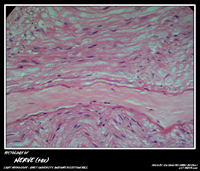

NERVE TISSUE